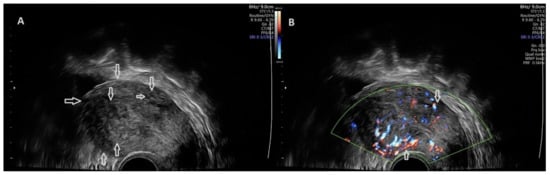

2.4. Strain Ratio Elastography Evaluation